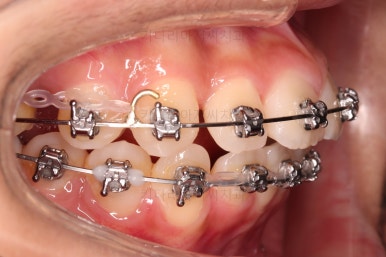

이번 환자분 같이 편악발치의 경우에는 윗니에만 발치 공간이 있고, 치아 사이즈의 부조화가 생겨서 발치 공간이 남거나 다 모아놔도 추후 재발이 되는 경우가 많습니다.

굉장히 디테일한 치료계획과 수행이 중요합니다.

이번 환자분도 다양한 테크닉으로 편악발치이지만 공간이 잘 줄어들 수 있게끔 치료해 나갑니다.

입매, 웃을 때의 입술선과 치열의 조화 등을 체크해줍니다.

디테일한 마무리를 하고 종료합니다.